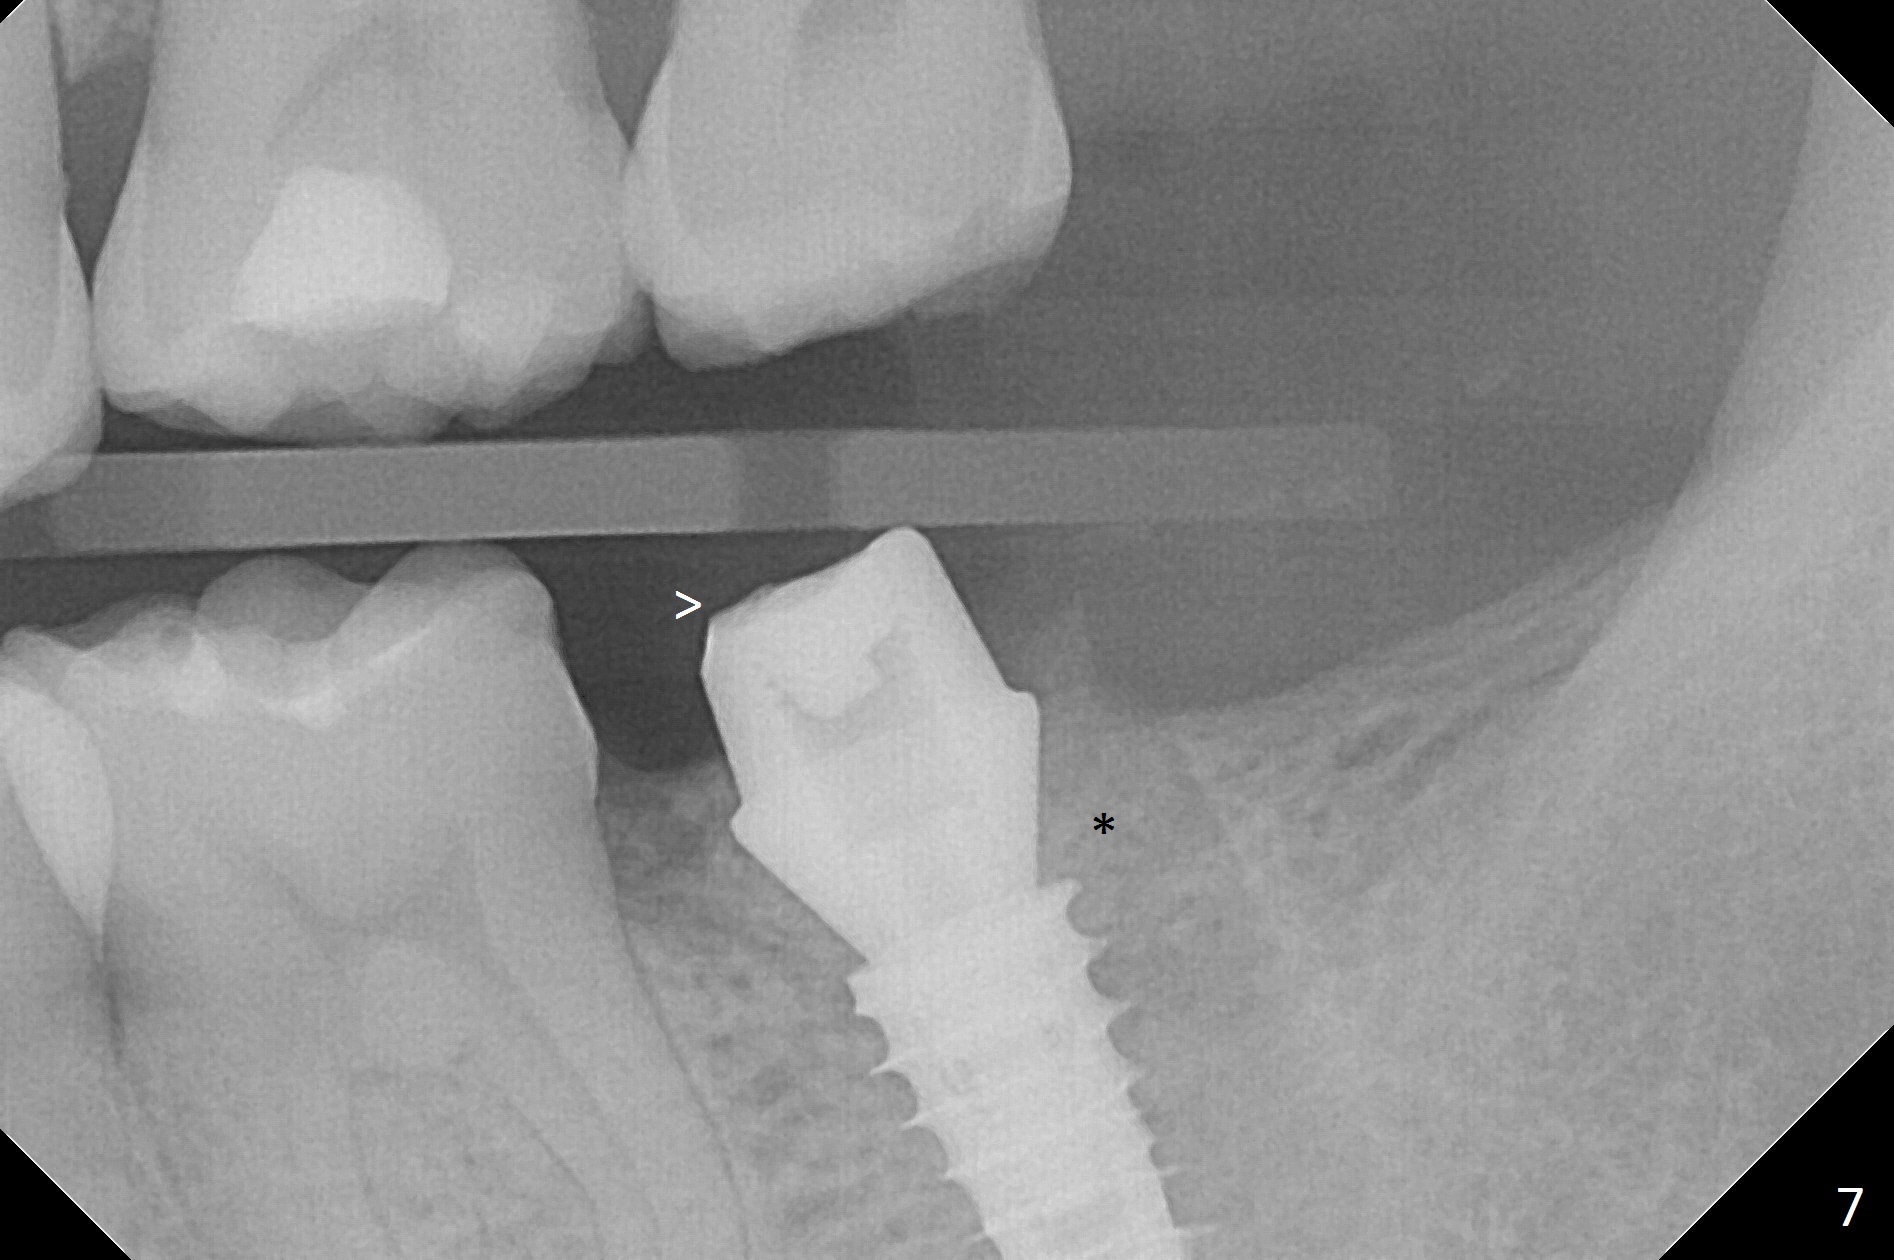

Following 4.8 mm MD, a 5x11 mm IBS implant is placed subcrestal circumferentially (Fig.6 with 50 Ncm). >: prepared abutment; *: bone graft.